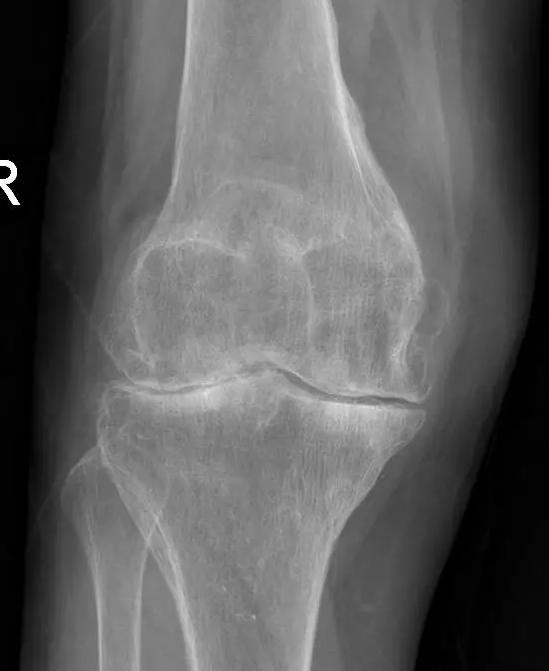

晚期:骨关节炎表现为膝关节明显疼痛,休息后常无缓解,伴有活动受限,可并发畸形,X 线片可见关节周围有明显的骨赘形成,或可见游离体,关节间隙明显狭窄,甚至消失。

对于晚期(重度)骨关节炎,保守治疗无效时,要积极考虑手术治疗。目前效果最佳的手术方式即为关节置换手术,其他手术方式如关节融合手术等效果较关节置换术相差较大,已不在临床广泛使用。关节置换手术的目的是缓解患者疼痛,矫正关节畸形,恢复关节功能,恢复正常生活。对于老年人来说,积极的手术治疗可以有效恢复其日常生活,避免因疼痛及活动障碍导致患者扶拐或坐轮椅,有效减少因缺乏运动导致的心肺功能障碍及精神问题发生。经过几十年的发展,目前关节置换技术已十分成熟,临床上目前采用的微创技术,手术创伤小,术中出血非常少,术后第二天患者即可下地行走,三月之后即可恢复正常生活及功能。至于人工假体使用寿命,目前进口关节多为20-30年,能满足60-70岁患者的需求。需要注意的是,在行关节置换手术之后,患者仍需要进行积极的康复治疗,包括关节活动度及周围肌力的锻炼等,这样才能达到最佳的手术效果。

术前片: